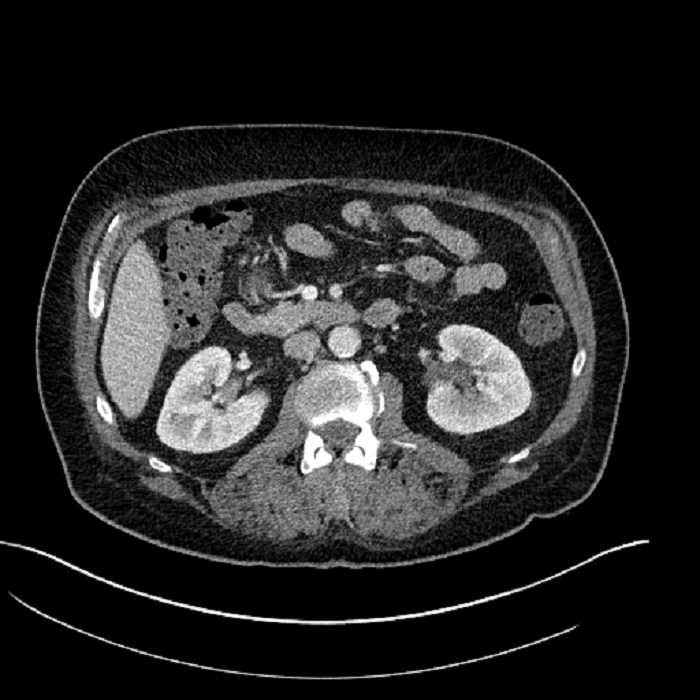

• Large fluid density structure in hepatic segments 7 and 8 measuring 10 x 7 x 7 cm with internal septation and circumferential ill-defined low density compatible with edema

• Peripherally enhancing subcapsular collections along the anterior margin of the left hepatic lobe measuring 3 x 1 cm and 2 x 1 cm

• Clearly marginated fluid density structure in segment 7 and several other scattered tiny hypodensities, which likely represent cysts

Acute sigmoid diverticulitis complicated by a small contained perforation and a large abscess in the right hepatic lobe. Additional small subcapsular abscesses along the anterior margin of the left hepatic lobe.

• The classic CT imaging appearance is a double target sign with internal low density surrounded by an internal enhancing rim (capsule) and a low density external rim (edema)

Hepatic abscess showing the double target sign with low density internally surrounded by a thin inner enhancing rim (red arrow) and ill-defined outer low density rim (yellow arrow). Blue arrow indicates an internal septation. Red arrows: additional smaller subcapsular abscesses. Red arrow: focal contained perforation associated with diverticulitis.